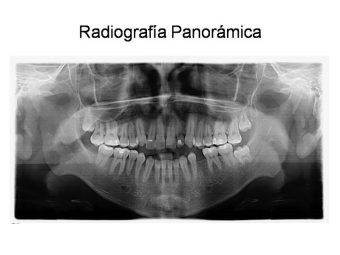

Casos y procedimientos

Envíado por Dr. Francisco Iván Ordóñez Carranza